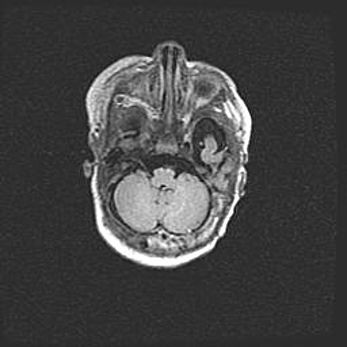

Подострая гематома правой гемисферы мозжечка.

Наружная гидроцефалия.

Возраст: 15 дней

Вес: 3100 г

Пол: женский

Окружность головы: 37 см

Срок гестации: 35-36 недель

При открытой наружной форме гидроцефалии у новорожденных расширяются и переполняются субарахноидные пространства.

Кровоизлияния в мозжечок имеют две клинико-анатомические формы: полушарные гематомы и кровоизлияния в червь.

К появлению этой патологии может привести: повреждения головного мозга, возникающие в результате асфиксии и гипоксии плода при беременности, или травмы во время родов. Редко гематома мозжечка может быть результатом первичной коагулопатии и сосудистой мальформации, диссеминированном внутрисосудистом свертывании, изоиммунной тромбоцитопении.